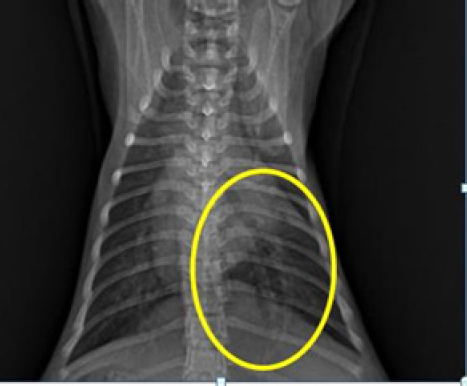

The outcomes of the X-ray investigation revealed the occurrence of discoloration in the abdominal cavity, accompanied by a noticeable progression in opacity. This phenomenon is commonly attributed to the emergence of fluid in the abdominal cavity (Figs. 2 and 3).

Fig. 2. Thoracic radiograph of Hiro’s cat in a dorso ventral (DV) changes in vascular patterns with dilatation of the pulmonary arteries and veins caudals.

The X-ray findings reveal a change in opacity in a section of the abdominal cavity, indicating an increase in radiopacity and the presence of ascites, or fluid buildup. Ultrasound imaging of the same area reveals anechoic regions between organs, which is a sign of fluid accumulation (Prajapati et al., 2022). Ascites are a symptomatic condition that occurs when fluid, both transudate and exudate, leaks into the space between the peritoneum and visceral layer of the abdominal cavity (Tilley et al., 2021). This is often a result of congestive heart failure or impaired venous flow and may cause cats to experience lethargy, abdominal distension, discomfort upon palpation, anorexia, vomiting, weight gain, scrotal or prepuce edema, and pain while lying down. Hypoalbuminemia, or low levels of albumin in the blood, is a contributing factor to ascites, as it reduces plasma osmotic pressure and increases vascular permeability, leading to fluid leakage from blood vessels into the abdominal cavity (Restijono et al., 2020).

Following changes occur in the caudal pulmonary arteries and veins or vascular patterns observed in the dorsoventral view of the X-ray position, specifically alterations in size. The pulmonary veins and arteries caudalis exhibit dilation, resulting in a vessel diameter larger than the IXth rib diameter, this is consistent with previous research, which states that enlargement of the left atrium and pulmonary veins is one of the symptoms of CHF in cats (Guglielmini and Diana, 2015; Bernes et al., 2020). The dilation of pulmonary arteries and veins is due to augmented pressure from systemic veins toward the right ventricle (Berry, 2010). The upsurge of pressure from systemic veins toward the right ventricle is caused by the improper blood circulation process in the right atrium and ventricle, leading to a small output of blood from the ventricles and the retention of blood in the heart chambers at the end of systole, which increases. This condition increases hydrostatic pressure, leading to the dilation of pulmonary arteries and veins (Triakoso, 2020). The high hydrostatic pressure causes fluid leakage from veins into pleural and peritoneal spaces, and potentially into pericardium and peripheral interstitial tissues. Ascites occur when fluid leakage surpasses the lymphatic system’s capacity (Tilley et al., 2021).